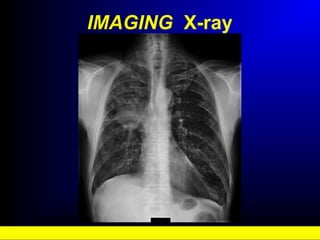

IMAGING X-ray

• #20 Non-small cell lung cancer X-ray: This X-ray shows an irregular mass (approximately 5cm x 4cm) at the right hemi thorax infiltrating into the adjacent mediastinum. Some mediastinum lymphadenopathy is present leading to a narrowing of the trachea. X-rays can give an approximate location of the tumour and an indication of the tumour size. Straight and lateral views are usually required to provide a complete picture of the depth of the tumour.